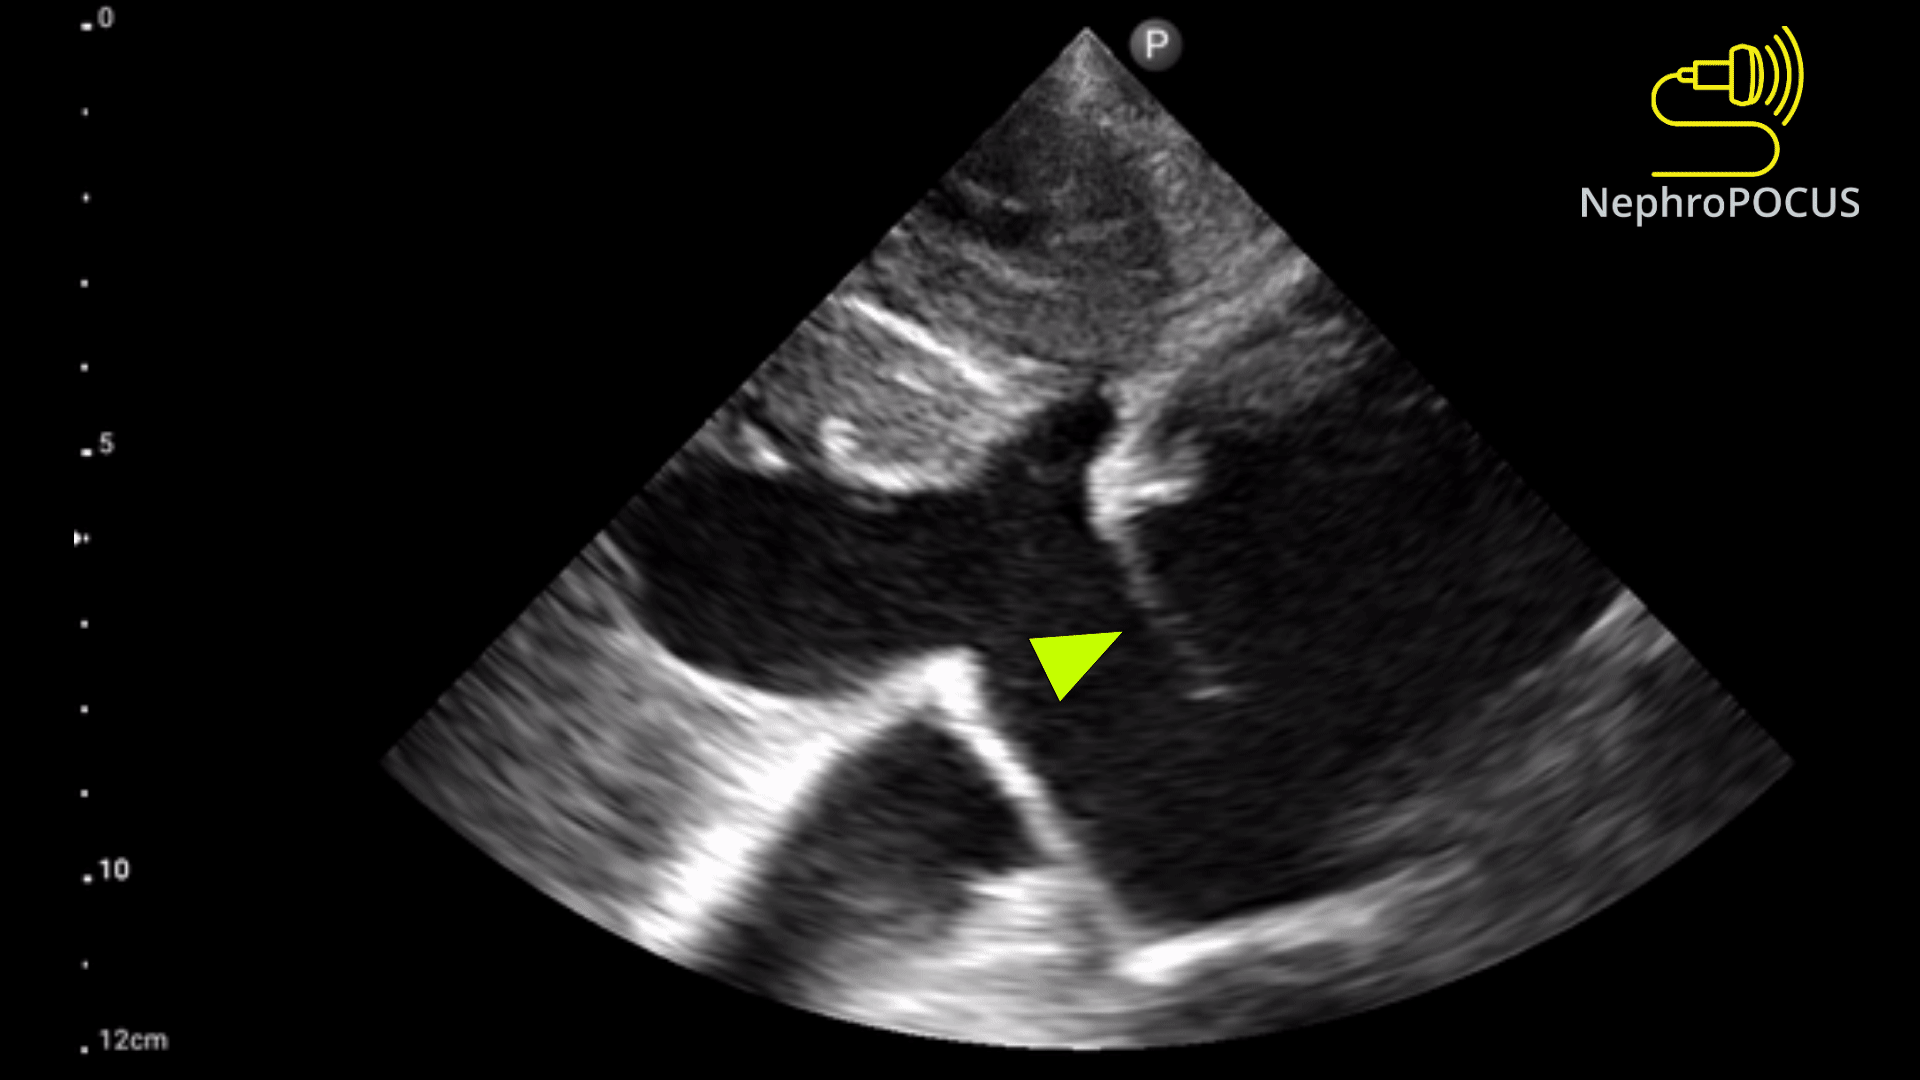

Pseudoaneurysm

What is seen in the 2D image?